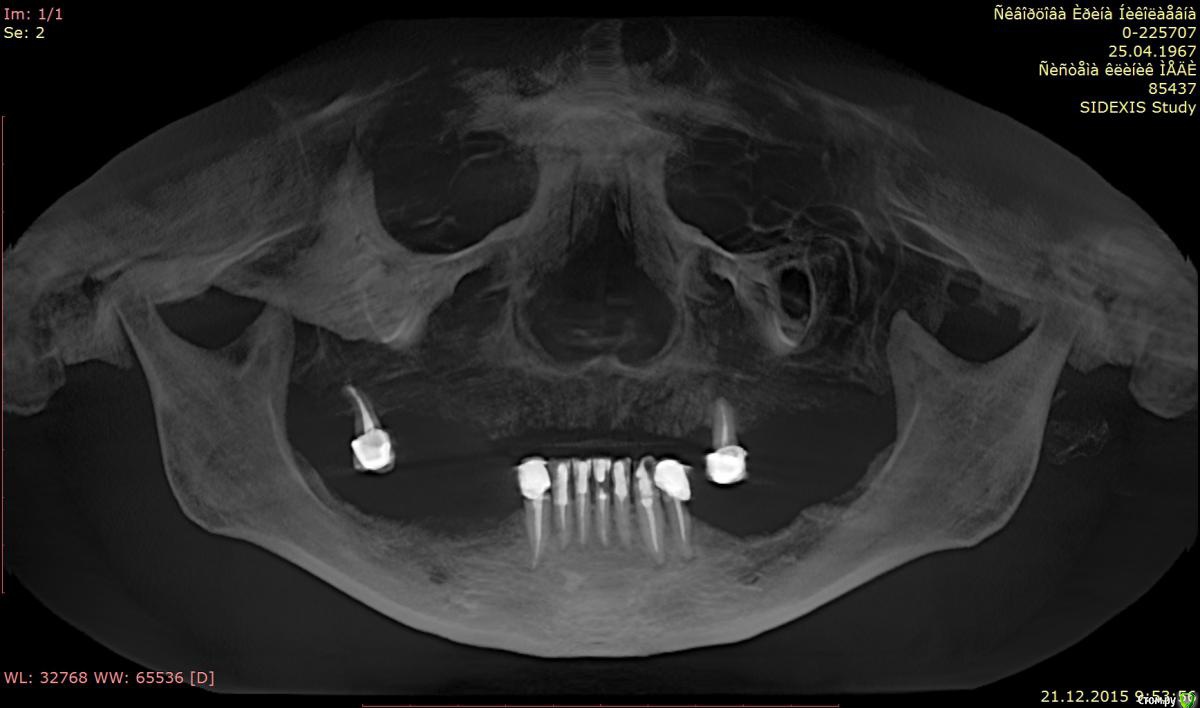

Tushka Опубликовано 4 января, 2016 Поделиться Опубликовано 4 января, 2016 Здравствуйте. Пациент женщина 49 лет, есть серьезные проблемы.Сейчас съемные протезы на обе челюсти. На верхней челюсти нет костной ткани. На нижней челюсти 1мм костной ткани.Хотим сделать несъемные протезы, на обе челюсти. Есть снимки DICOM, архив ZIP можно загрузить из Google Drive по ссылкеhttps://drive.google.com/file/d/0B8QE61hrloGVYTBsTW9hUzd0ejA/view?usp=sharing Пока все врачи рекомендуют скуловые имплатны - зигому Есть ли еще варианты решения проблемы? Заранее благодарю за ответ. Ссылка на комментарий

Tushka Опубликовано 5 января, 2016 Автор Поделиться Опубликовано 5 января, 2016 (изменено) Снимки прикрепил во вложении.Экспортировал их из КТ, ссылку на которую давал, с помощью бесплатной программы RadiAnt DicomНа всякий случай эти два снимка и еще 512 экспортировал в стандартный формат jpeg и выложил в общий доступ по ссылке https://drive.google.com/file/d/0B8QE61hrloGVaHJTczBiMjlNSGM/view?usp=sharingСпасибо! Изменено 5 января, 2016 пользователем Tushka Ссылка на комментарий

Evikrol Опубликовано 5 января, 2016 Поделиться Опубликовано 5 января, 2016 Вы не совсем то выложили, но наверху кажется можно all on 4 Ссылка на комментарий

IvanK Опубликовано 6 января, 2016 Поделиться Опубликовано 6 января, 2016 Можно обойтись и без скуловых, но с наращиванием кости 1 Ссылка на комментарий